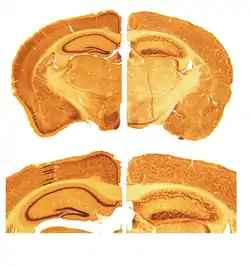

A reeler is a mouse mutant, so named because of its characteristic "reeling" gait. This is caused by the profound underdevelopment of the mouse's cerebellum, a segment of the brain responsible for locomotion. The mutation is autosomal and recessive, and prevents the typical cerebellar folia from forming.

Cortical neurons are generated normally but are abnormally placed, resulting in disorganization of cortical laminar layers in the central nervous system. The reason is the lack of Reelin, an extracellular matrix glycoprotein, which, during the corticogenesis, is secreted mainly by the Cajal-Retzius cells. In the reeler neocortex, cortical plate neurons are aligned in a practically inverted fashion (‘‘outside-in’’). In the ventricular zone of the cortex fewer neurons have been found to have radial glial processes.[1] In the dentate gyrus of hippocampus, no characteristic radial glial scaffold is formed and no compact granule cell layer is established.[2] Therefore, the reeler mouse presents a good model in which to investigate the mechanisms of establishment of the precise neuronal network during development.

Key pathological findings in the Reeler brain structure

- Inversion of cortical layers.

- Dispersion of neurons within cortical layers.

- Decreased cerebellar size.

- Failure of preplate to split